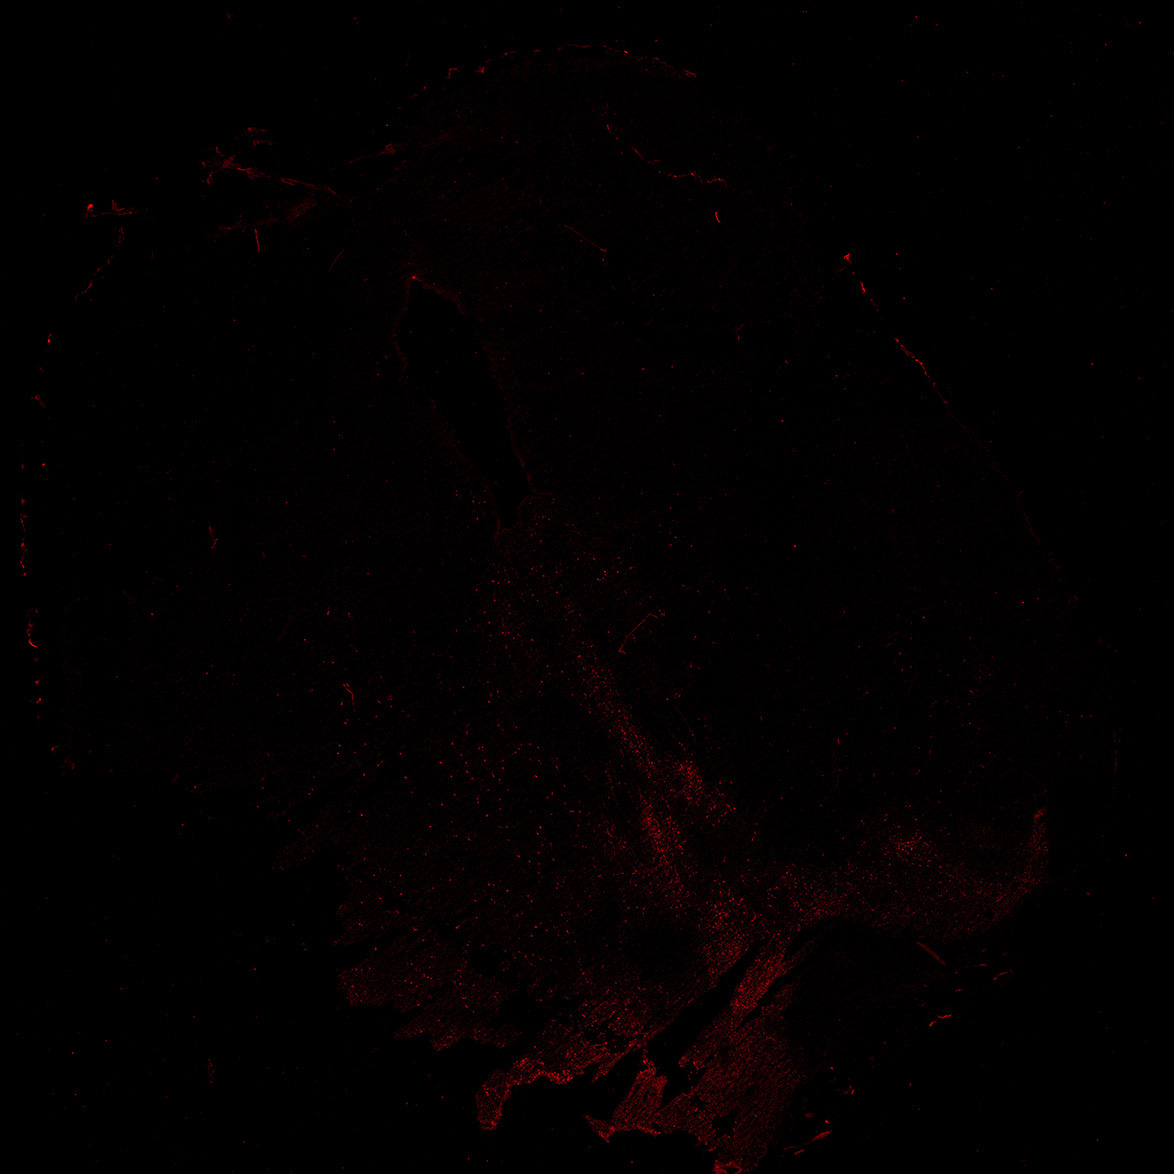

TH

19PCW human midbrain